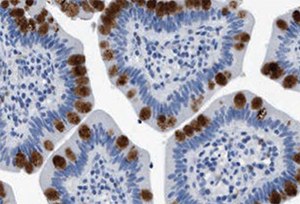

Figure 4.Immunohistochemistry. Anti-HABP2: Cat. No. HPA019518: Immunoperoxidase staining of formalin-fixed, paraffin-embedded human small intestine shows strong intracellular proteinaceous material positivity in glandular cells.